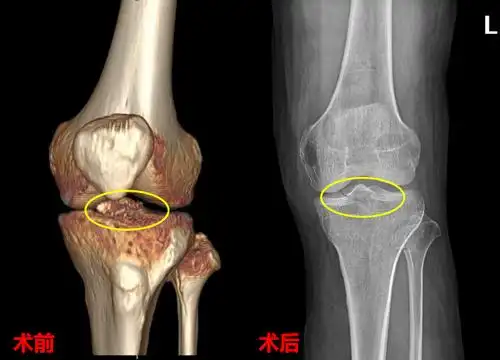

疼痛,肿胀,活动受限,在外院做膝关节x线检查发现是左侧胫骨髁间棘骨折

胫骨髁间棘

胫骨髁间棘骨折

胫骨髁间棘骨折术前dr片!